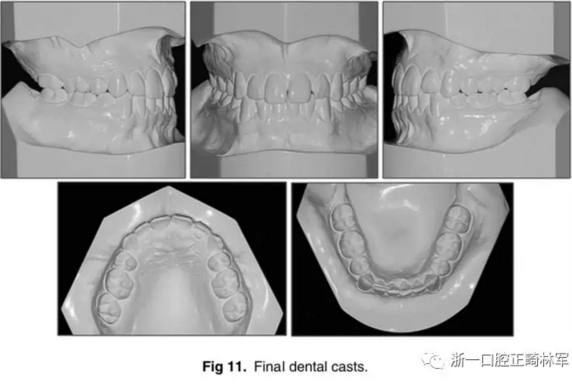

口內(nèi)相及模型:雙側(cè)磨牙、尖牙I類關(guān)系,良好的牙尖交錯關(guān)系,覆合、覆蓋正常。

影像學:全景片示:牙根平行度可。頭顱側(cè)位片及疊加圖示:顯著的骨性、牙性改變;其中,最大的改變?yōu)樯舷骂M位置關(guān)系,改變了7mm;由此帶來的改變?yōu)锳NB角從-4°變?yōu)?°,Wits值由-10mm變?yōu)?1.5mm,上頜突度減?。ˋ-NPer,3mm),上下頜不調(diào)改善(Co-A-Co-Gn,41mm),從而使側(cè)貌更為平直;下頜磨牙遠中移動,無伸長、傾斜,反映了下頜整體的遠中移動;上下切牙傾角糾正(1:NA,7mm、25°; 1:NB,4.5mm、20°; IMPA,78°),從而改善了在基骨中的位置。

功能:前伸合的切牙引導(dǎo)與側(cè)方合的尖牙引導(dǎo)得以實現(xiàn)。

側(cè)貌:上唇突度增大4mm(至S線0mm),整體側(cè)貌更為和諧。

5年隨訪:治療結(jié)果保持穩(wěn)定,無明顯復(fù)發(fā),但下頜中線有輕微偏移;下頜磨牙位置始終保持穩(wěn)定。